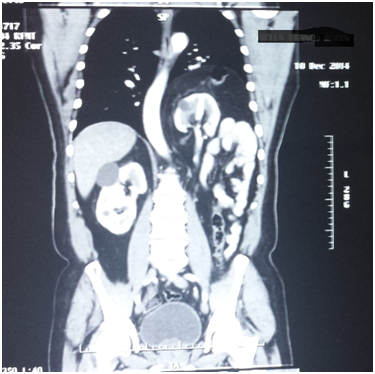

The patient attends the urology outpatient clinic because the previous week he had presented lumbar pain radiating to the right flank as well as the right iliac fossa, intermittent, without fever but with occasional constipation and flatulence. The patient attends to a private’s hospital ER and is prescribed with analgesics, however, 24hours later he presents a new pain condition and attends the same center and undergoes further complete laboratory tests that did not present any alterations. After a throaco abdominal Computerized Axial Tomography with contrast, the presence of intra thoracic ectopic kidney and left diaphragmatic hernia is observed and with a progress caused by the medical treatment administered in the hospital, the patient attends the Urology service due to the presence of left ectopic kidney. Upon arrival to the clinic, the asymptomatic patient does not show any urological pathology and turns out with normal laboratory results (Figure 1-4).

Figure 2 CT sacan show a left kidney near to the heart.